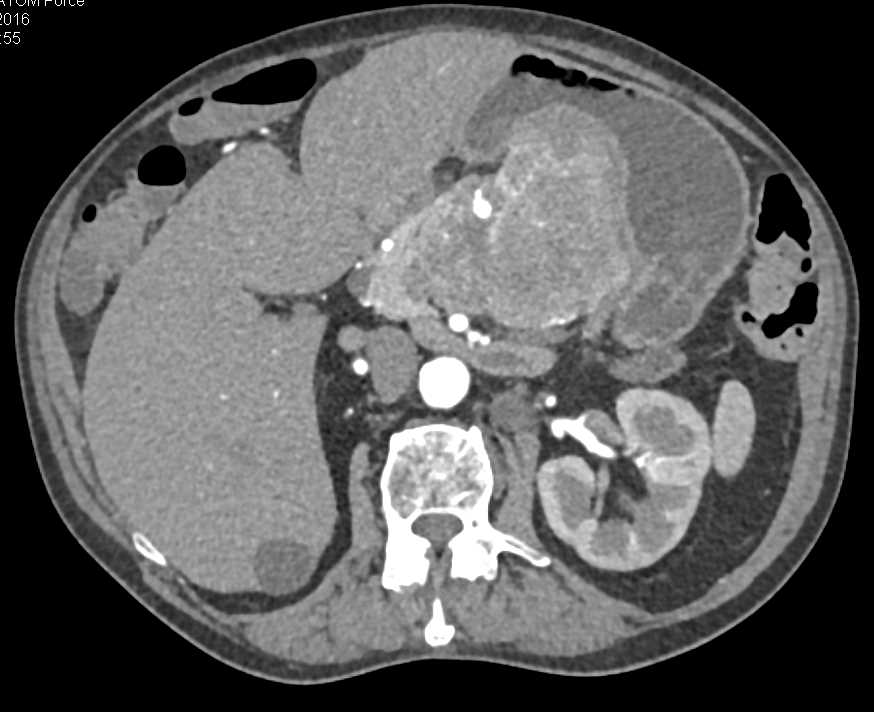

Pancreatic Neuroendocrine Tumor (PNET) in the Head of the Pancreas